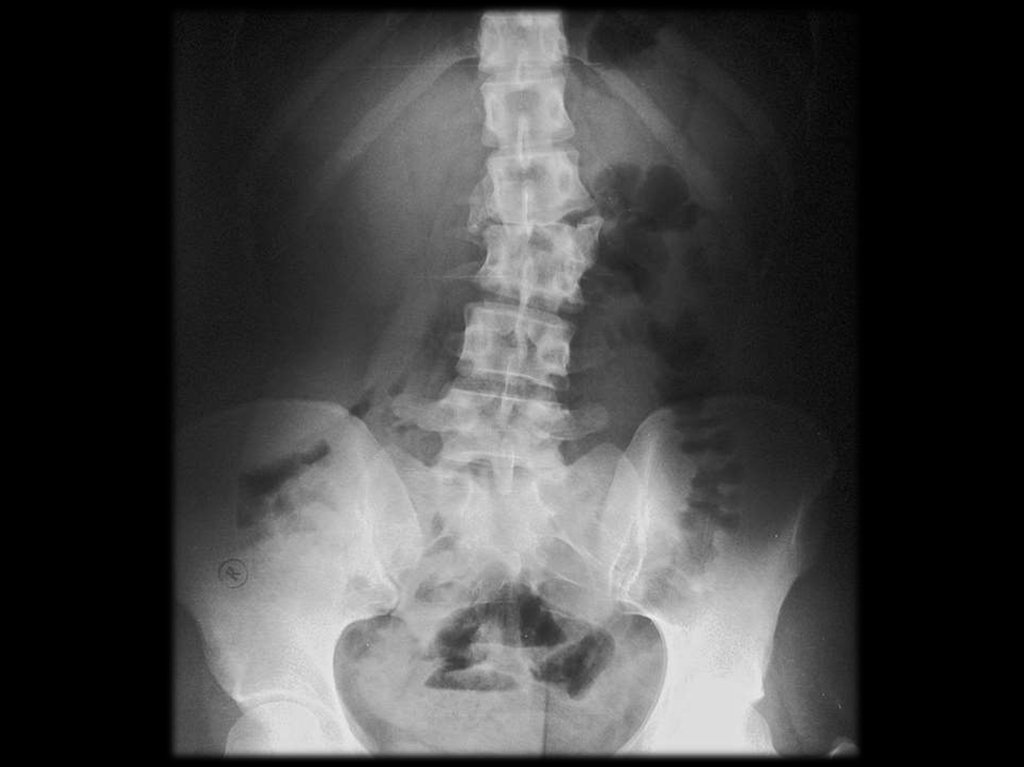

6. Классификация

Шейный

Грудной

Поясничный

Крестцовый

Распространённый – когда заболевание

охватывает

два

и

более

отделов

позвоночника